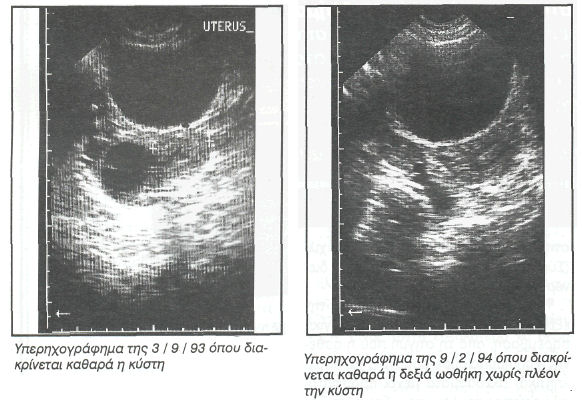

Η ασθενής που προσήλθε, 27 ετών, εμφάνισε μόρφωμα, κυρίως κυστικό, στη δεξιά ωοθήκη, διαστάσεων 4X4 χιλ. (Σύμφωνα με υπερηχογράφημα που διενεργήθη στις 3 / 9 / 93)

Αξιολογώντας ως θετικές αυτές τις αντιδράσεις συστήθηκε επανάληψη του υπερηχογραφήματος γεννητικών οργάνων στις 9/2/94 (περίπου 4 μήνες μετά το πρώτο). Η ανυπαρξία κυστικού μορφώματος επιβεβαιώνει τη δυνατότητα που έχει η ομοιοπαθητική θεραπεία να ανταποκρίνεται με επιτυχία ακόμη και στην ύπαρξη ανατομικών προβλημάτων. Επιβεβαιώνεται έτσι, ότι η μη αποδοχή της ομοιοπαθητικής θεραπευτικής δεν οφείλεται στην έλλειψη αποτελεσματικότητας της βέβαια, αλλά στον αποκλεισμό από την κοινωνία οποιασδήποτε διαφορετικής παράδοσης που στέκεται κριτικά ή αντιθετικά στην επικρατούσα επιστημονική άποψη. Ο μεγαλύτερος όμως κίνδυνος φαντάζει να είναι η διαφαινόμενη αποδοχή αυτής της εναλλακτικής μεθόδου (όπως και των υπολοίπων) και η περιθωριοποίηση τους ως συμπληρωματικών προς την κρατούσα ιατρική συστημάτων, έτσι ώστε να ευνουχίζεται η σημαντική δυναμική που μπορούν να προσφέρουν και σε προσωπικό και σε συνολικώτερο επίπεδο. Το όφελος για την συγκεκριμένη ασθενή δεν είναι απλά η αποφυγή μιας χειρουργικής επέμβασης, αλλά επιπλέον η συνολική άνοδος του επιπέδου υγείας που εξασφαλίζει και την άμεση και αιτιολογική λύση του προβλήματος της, αλλά και την διατήρηση ενός καλύτερου επιπέδου υγείας στο μέλλον. Ματαιώνεται επίσης και εκείνη η ιατρική λογική, που ενώ μέσα από την πρακτική της (χρήση ορμονών στη συγκεκριμένη περίπτωση) τείνει να δημιουργεί ένα πρόβλημα, νομιμοποιείται να οδηγείται στην λύση του προβλήματος μέσα από μια ακόμα πιο βίαιη και τυφλή (μη αιτιολογική) χειρουργική επέμβαση.